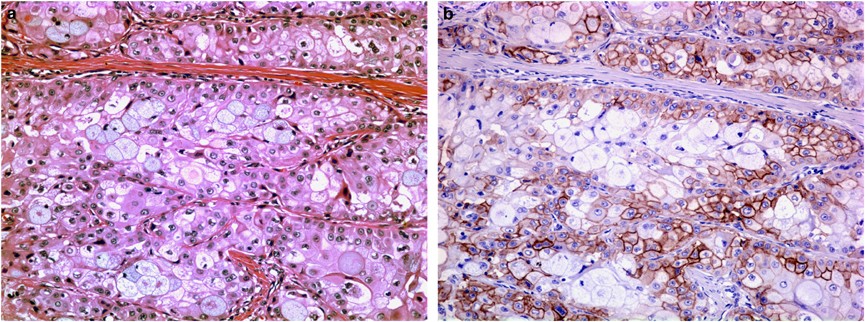

Intermediate power photomicrograph of a grade 2 mucoepidermoid carcinoma ((a) H&E, × 200). The expression of EGFR is seen mainly in the squamous and intermediate cells with sparing of goblet cells ((b) EGFR, × 200).